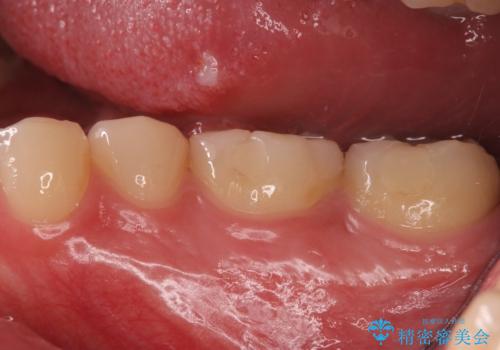

奥歯がしみる 神経を温存する治療

- 奥歯がしみるとのことで来院されました。

検査の結果、古い詰め物の裏側に虫歯ができていること(二次う蝕)が確認されたため、治療していくこととなりました。

虫歯が大きくても、今回のように神経を温存することができる場合があります。